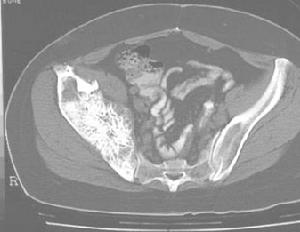

檢查對腎盂癌診斷有重要意義。表現為腎盂內實性占位,晚期可發現浸潤周圍器官和淋巴結。對輸尿管作全程掃描亦有助於診斷輸尿管癌,但套用有一定局限,可作為尿路造影的補充檢查。CT對早期輸尿管腫瘤的診斷意義不大,不能作為輸尿管癌的常規診斷方法,但對晚期腫瘤的分期及了解腫瘤浸潤範圍有重要意義

根據X線影像如充盈缺損區邊緣連續性和形態、充盈缺損區造影劑殘留等情況,可以估計相應的腫瘤大體形態和腫瘤分期,並進一步推測腫瘤的分級。是上尿路移行細胞癌的主要診斷方法。由於10%~30%腎盂癌和50%輸尿管癌IVU完全不顯影,若逆行造影失敗會影響診斷和處理方法的制定。MRU能良好解決該問題,並有不需造影劑的對比和避免放射性損害等優點。